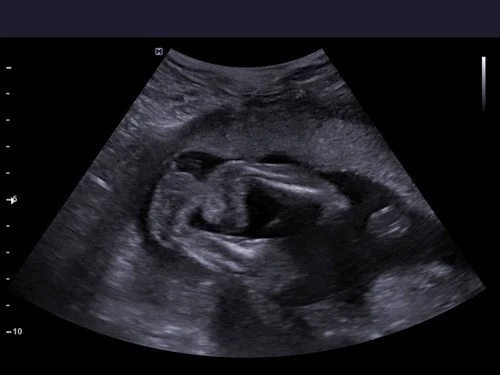

Clubfoot can be diagnosed during pregnancy through ultrasound scan is usually done between 16 to 24 weeks. The scan will show if the foot is in an abnormal position and if it’s associated with others anomalies.